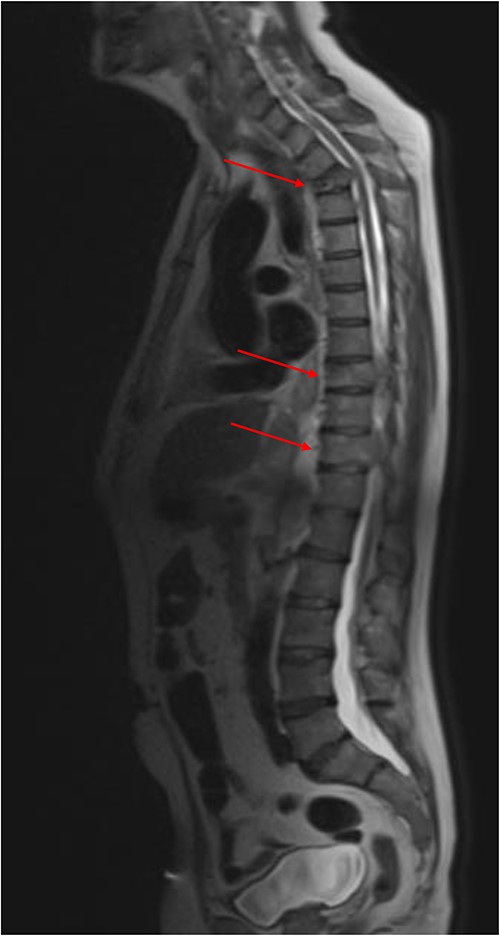

MRI revealed extensive bony metastatic disease involving the anterior and posterior elements of the spine and sacrum (Fig. 2). Malignant compromise to the spinal canal at T3, T9 and T11 was noted, as well as extensive malignant adenopathy including the mediastinum and both supraclavicular fossae. Dexamethasone with proton pump inhibitor cover, and palliative radiotherapy to the spine was given for MSCC. Under ultrasound guidance, the left supraclavicular fossa nodes were biopsied and sent for histological analysis.

Sagittal MRI whole-spine demonstrating extensive bony metastatic disease. Malignant compromise to the spinal canal at T3, T9 and T11 (red arrows).